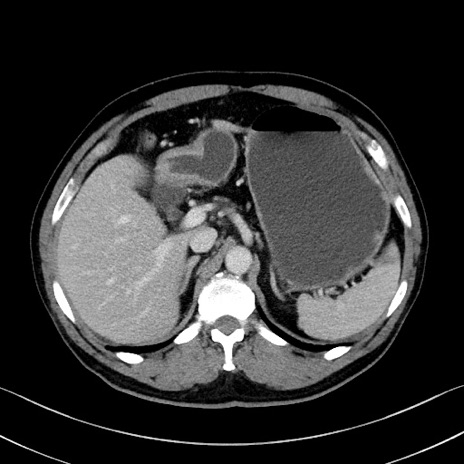

症例35(横断像)

【症例】70歳代 男性

【主訴】腹部膨満、嘔吐

【現病歴】昨日より腹部膨満感出現。本日増悪し、仙痛出現。嘔吐あり、受診。

【既往歴】糖尿病、胆摘後

【身体所見】BP 149/80mmHg、HR 74/min、BT 35.9℃、腹部:膨満、軟、圧痛なし。腸雑音減弱あり。上腹部正中切開瘢痕あり。

【データ】WBC 13500、CRP 1.72